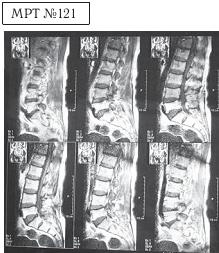

На МРТ № 121 общий снимок магнитно-резонансной томографии, на котором наблюдается полное отсутствие секвестрированной грыжи межпозвонкового диска в сегменте LIV-LV Состояние поясничного отдела позвоночника после одного курса лечения методом вертеброревитологии.